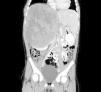

Niña de 5 años que presentaba abdomialgia difusa de 15 días e incremento del perímetro abdominal detectado hacía 24h. Mostraba distensión abdominal y se palpaba masa de consistencia firme, no dolorosa, en mesogastrio e hipocondrio y flanco derechos que sobrepasaba 10cm el reborde costal. Se encontró hipertensión arterial. Se detectó LDH de 930 UI/l y PCR de 40mg/l, siendo el resto de los valores analíticos normales. En la ecografía abdominal mostraba una masa abdominal de 15 x 13 x 15cm en hemiabdomen derecho y la radiografía de tórax elevación de hemidiafragma. En la TAC con contraste se observó una masa de 17 x 13 x 14cm con captación heterogénea, dependiente de polo superior de riñón, que desplazaba hígado, aorta y vena cava a la izquierda, comprimiendo ésta (fig. 1). La masa rebasaba la línea media (fig. 2). Tras la confirmación histológica se inició quimioterapia en centro de referencia.